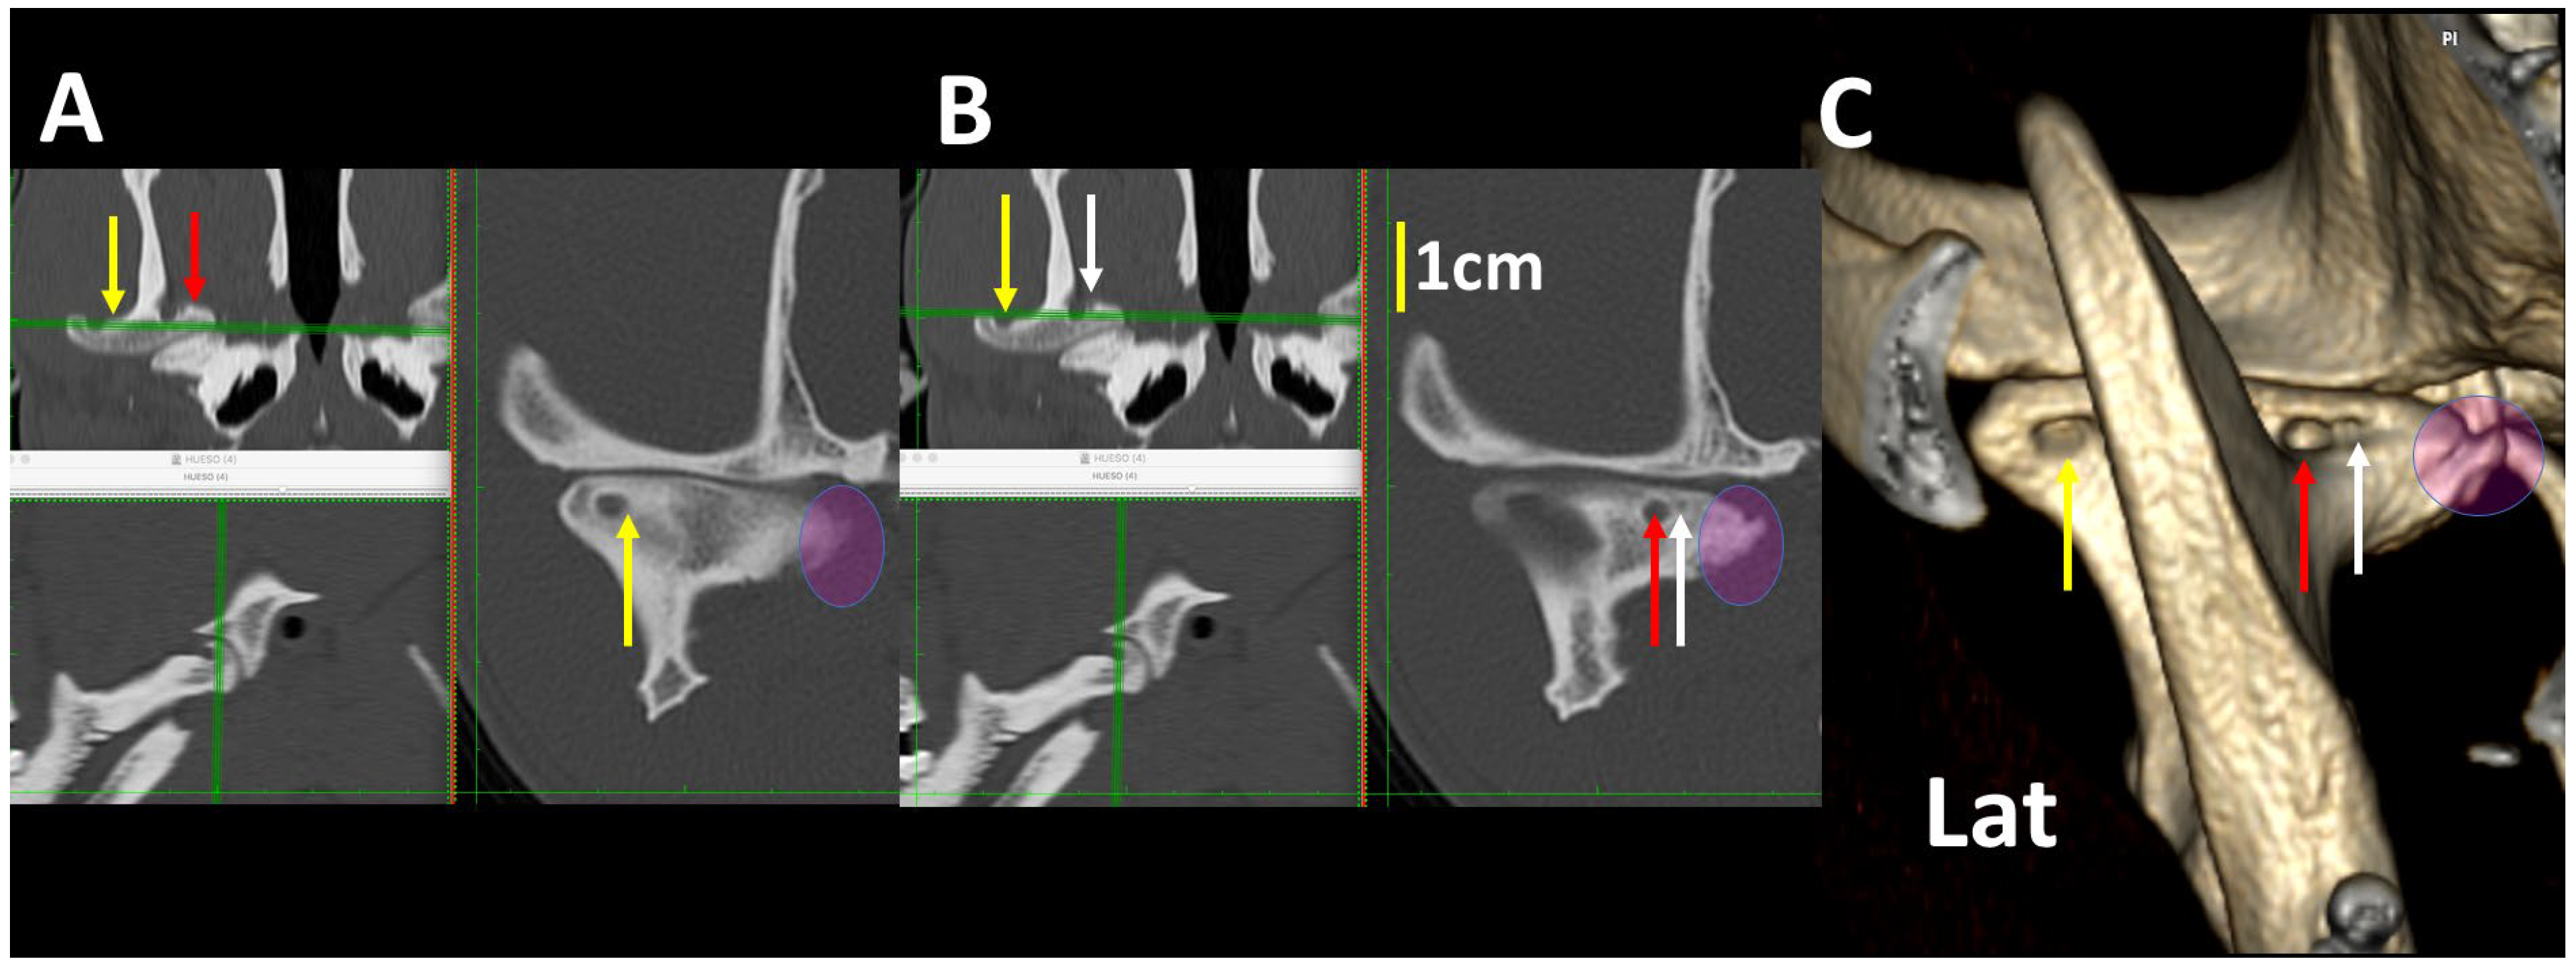

3.4. A Pictorial Essay of 3DVR Images in Some Pathological Cases